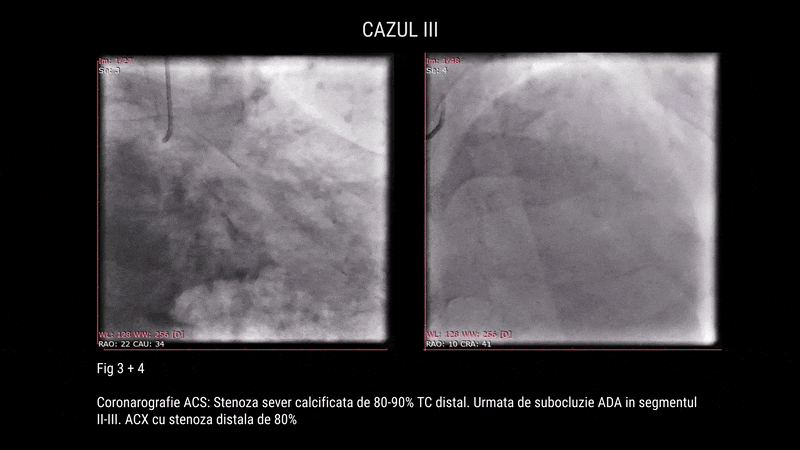

Al treilea pacient, în vârstă de 62 de ani, hipertensiv și dislipidemic, cunoscut cu leziuni tricoronariene (ocluzii pe ACD, stenoze critice pe LAD și ACX), a fost internat pentru angioplastie. Intervenția a presupus rotablație pe ACX și TACS–LAD, cu implantare de 4 stenturi DES facilitată de rotablație, POT și Kissing Balloon. Aspectul angiografic final a fost satisfăcător, cu flux TIMI 3 menținut și fără complicații.